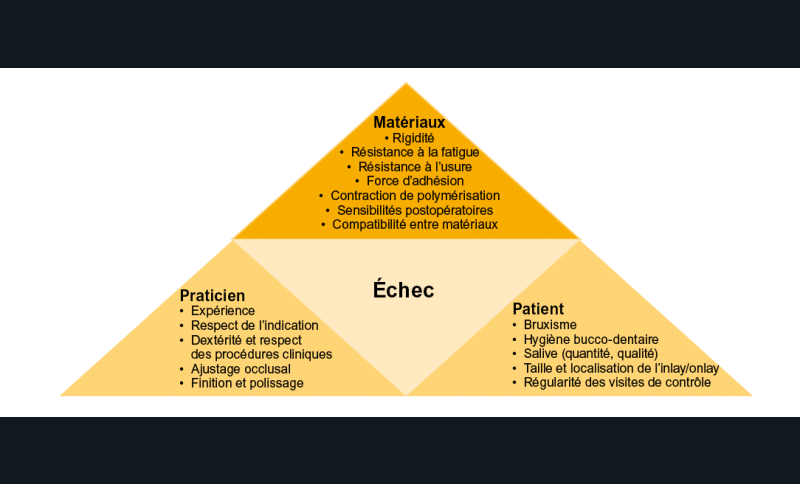

La longévité des restaurations indirectes dépend de nombreux facteurs qui peuvent être regroupés en trois grandes classes (fig. 1) :

– les facteurs liés au patient,

– les facteurs liés au praticien,

– les facteurs liés aux matériaux.

Parmi ces facteurs, ceux liés au patient ne sont identifiables qu’indirectement par l’anamnèse clinique, l’enseignement des mesures d’hygiène et l’information délivrée au patient.

Les facteurs que le praticien est en mesure de contrôler sont ceux relatifs aux limites des indications et des procédures cliniques et ceux relatifs au choix des matériaux utilisés.

L’influence relative de ces différents facteurs sur la longévité des restaurations est difficile à établir. La distinction entre les facteurs qui provoqueront une complication précoce de la restauration (facteurs liés au praticien) et ceux qui conduiront à une complication à plus long terme (facteurs liés au patient et aux matériaux) est néanmoins…